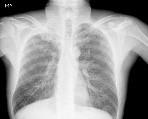

Table 3. Samples of CXR images from each dataset

Montgomery County, USA

Shenzhen, China

Konya, Turkey